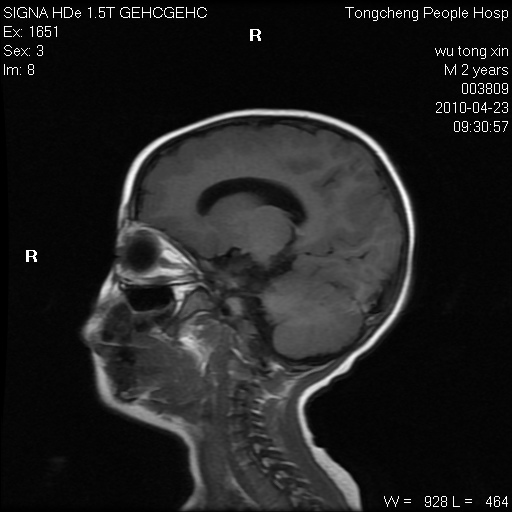

以下是引用赵物学在2010-4-25 12:43:00的发言:[br]巨脑回[br]侧脑室后角低密度影考虑hie或肾上腺脑白质营养不良?[br][br][本贴已被 赵物学 于 2010-4-25 12:51:28 修改过]

以下是引用gaoxiao在2010-4-25 16:54:00的发言:[br]巨脑回畸形。脑白质髓鞘化不良

以下是引用pujunzhi在2010-4-25 21:35:00的发言:[br]考虑 1双侧大脑皮质发育不良 2轻度脑积水 3双侧脑室后角旁片状长t1长t2信号,需继续观察,因为正常小儿此处脑白质的髓鞘化时间可以延迟到4-6岁,才显示正常。